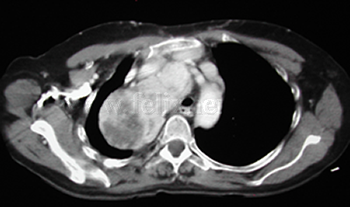

Timoma |